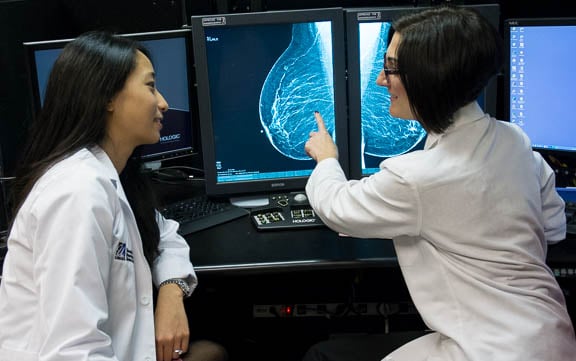

The UMass Chan Medical School Department of Radiology is a respected leader on all three fronts. Our talented faculty and advanced technology attract trainees and scientists who are among the best and brightest – offering the opportunity to work and train in a dynamic innovative environment which remains personal and accessible.

Our mission is simple: to bring scientific advances in medical imaging to clinical application. Our current major areas of focus include Interventional Neuroradiology, Biomarker Development, Molecular Imaging, Nuclear Medicine Physics, and Cell Biology. Learn more.

A superb faculty serving two hospital campuses, an array of complex, tertiary-care pathology across all major medical and surgical disciplines, today’s most advanced imaging technology and an annual volume of nearly 500,000 exams provide an exceptional, hands-on learning environment for residents and fellows.